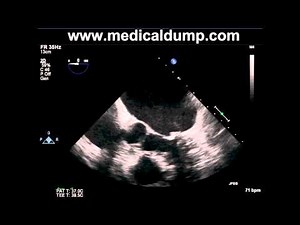

Left Atrial Appendage Closure (feat. Dr. Almany)